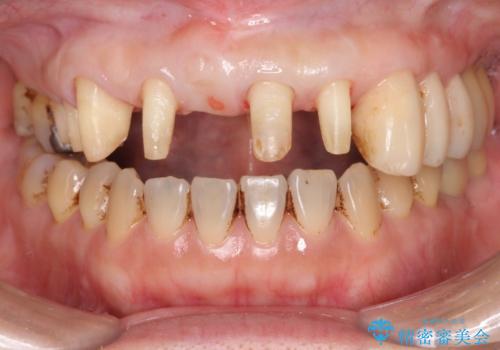

歯周病に対する全体治療

- 近医で「重度の歯周病です、入れ歯にする必要がある。」、と言われ入れ歯以外の方法がないか相談にみえられました。

再生治療、歯周外科を行うことで歯周病治療を行い、残すことのできる歯の歯周環境を整える。

残すことのできない歯は抜去したのち骨造成を含めたインプラント治療を行い、しっかりとした咬合関係を確立していきます。

治療期間はかかりましたが、しっかりと歯周病治療・インプラント治療を行ったおかげで歯周病の状態は非常に良くなり、安定した咬合関係を確立することができました。